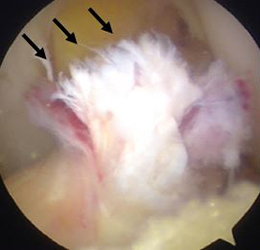

関節鏡視下半月板部分切除術・縫合術

本手術は内視鏡を用いて行うため、少数の小さい傷で低侵襲に行う事ができます。可及的に縫合し半月板の温存を試みますが、損傷形態によっては部分切除を選択します。リハビリは、術翌日より積極的に行い、スポーツ復帰や社会復帰に向け準備致します。

前方に逸脱した外側半月板を整復し縫合した。